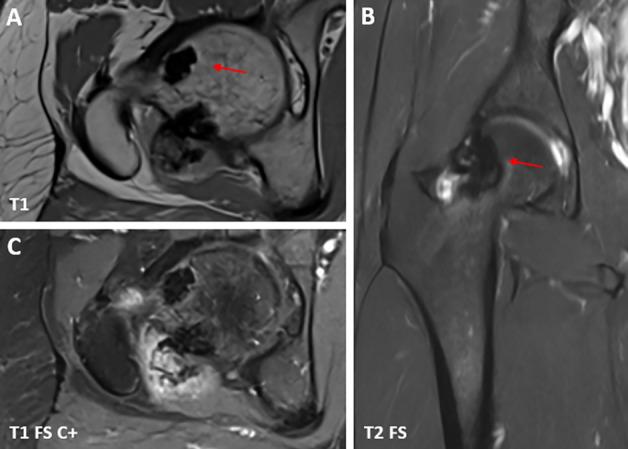

肢骨纹状肥大是一种罕见的骨硬化发育异常,其特征是皮质骨的骨膜侧和/或骨内膜侧出现硬化,导致骨轮廓呈波浪状增厚,类似“滴蜡”。